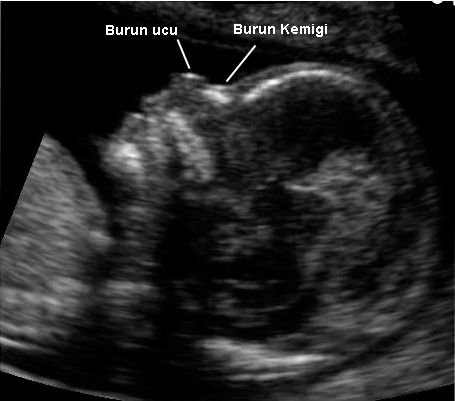

İkili test için yapılan ultrasonografi esnasında, down sendromu riskini anlamanın yollarından biri de bebeğin burun kemiğinin oluşup oluşmadığının gözlenmesidir. Hamileliğin 11 ile 13+6. haftaları arasında yapılan bu inceleme her ne kadar kesin sonuç vermese de yapılan incelemelerde down sendromlu bebeklerin burun kemiklerinin oluşmadığı bilindiği için burun kemiğin yokluğu yada inceliği incelenen bebeğin down sendromu olma olasılığını arttırmaktadır. Ancak bu durum tek başına bir sonuç değildir ve bazı insan ırklarının gebeliklerinde burun kemiğinin daha geç oluştuğu bilinmektedir.

14. haftadaki bir bebeğin burun kemiği incelemesi

Yapılan bir incelemede Trizomi 21 anomalisine sahip 59 bebekten 43'ünde (% 73) ve Kromozomları normal olan 603 bebeğin sadece 3'ünde (% 0,5) burun kemiğinin olmadığı gözlenmiştir. Kromozomu normal olan bebekler ile karşılaştırılıdığında trizomi 21 anomalisine sahip bebeklerin burun kemiğinin olmamasının oranı yaklaşık olarak 150 kat daha fazladır.